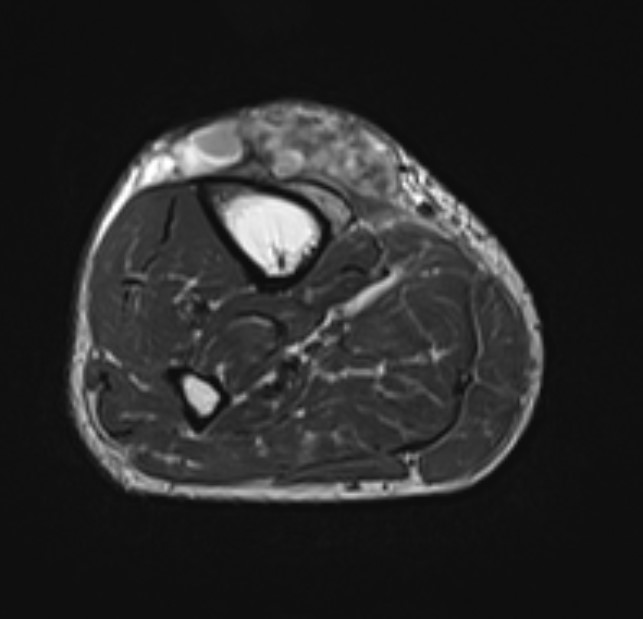

MRI

Anatomy / neurovascular involvement

Sarcoma knee